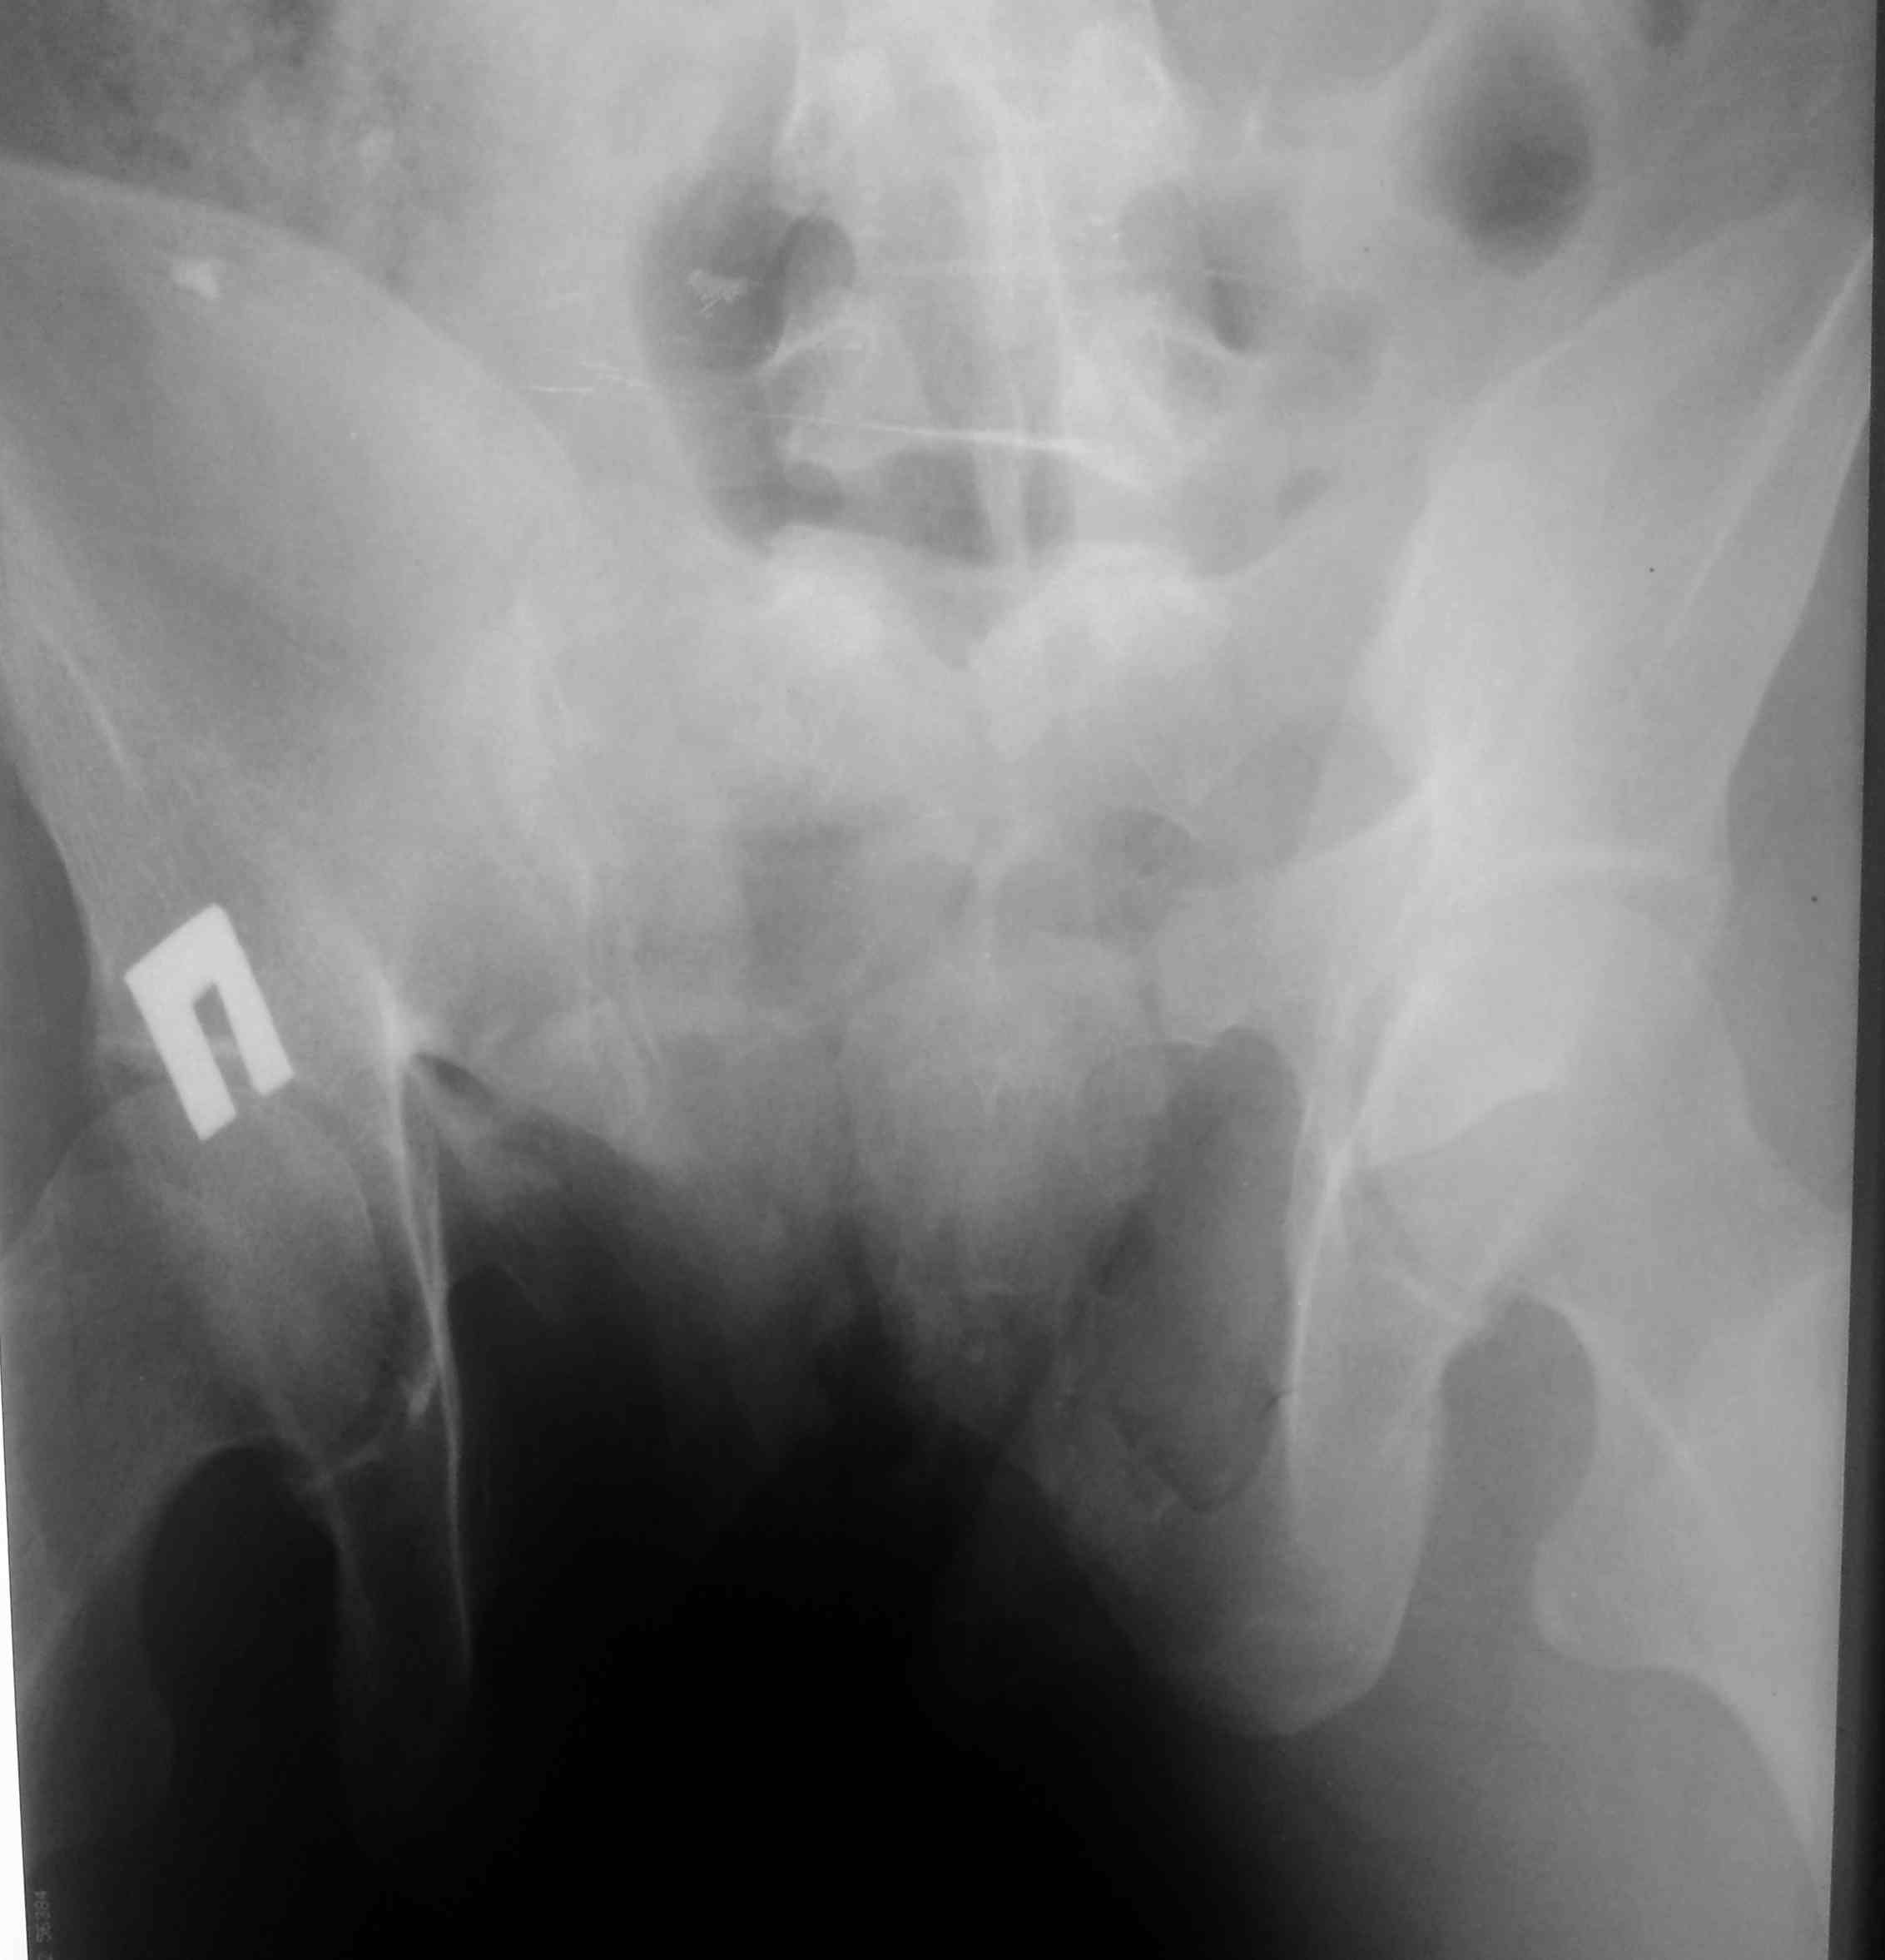

[Ortho] тяжелый таз

высылаю контрольные снимки на вытяжении, правую половину таза

подрепонировали вручную, за лево - скелетка. Дополнительно, левое плечо

- диафиз, множественные переломы ребер слева. Стала хуже по легким. Пока

план - при улучшении по легким - передняя рама + илиосакральные винты

справа, при улучшении - расслабляем переднюю раму, открыто синтезируем

подвздошную кость задним доступом, обратно затягиваем аппарат. Плечо -

когда получится